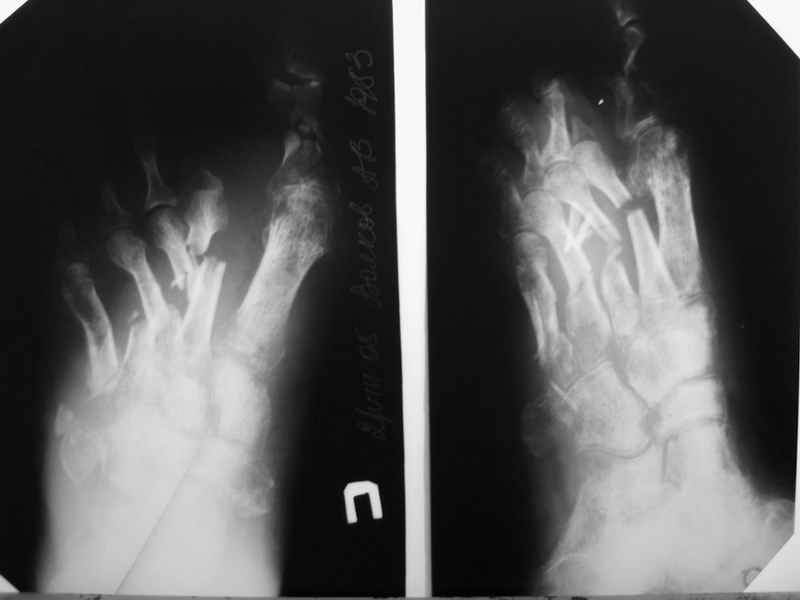

В продолжение темы конкретного больного. К сожалению, после достаточно длительной ходьбы несколько дней назад, появились классические признаки воспаления. Сегодня выполнил некрэктомию-дистальный отломок 2 плюсневой кости с остатком фрагмента основной фаланги- буквально плавали в гное. Рану тампонировал с левосином. Компенсации кровооброщения не наступило?

P.S. Перед операцией взял посев и на чувствительность, но ответ(в нашей лаборатории) скорее всего предсказуем-Staph aures. Посмотрим на чувствительность.

Здравствуйте, Тимур Вячеславович. Спасибо за живой интерес к проблеме: этапы к Вам понял. Насчет ампутации, я думаю, что больной еще не созрел, наоборот- полон оптимизма. Вот свежие рентгенограммы и стопа на 5 день после операции. Появились грануляции, но рана глубокая- 2-2,5 см. Хотелось бы узнать о Вашей тактике на ближайший период, если это возможно. С уважением, Алексей